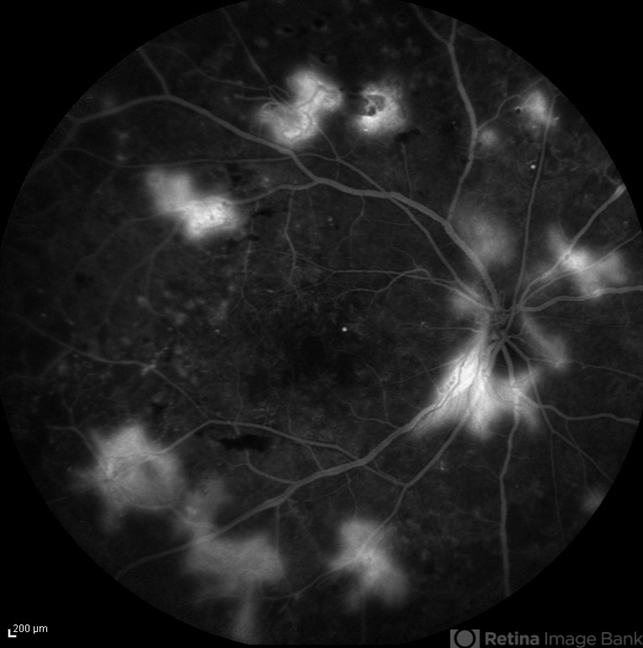

- proliferative diabetic retinopathy (PDR)

- FA image of the right eye of a diabetic patient with PDR . Leakage from the NVD and NVE foci are visible.